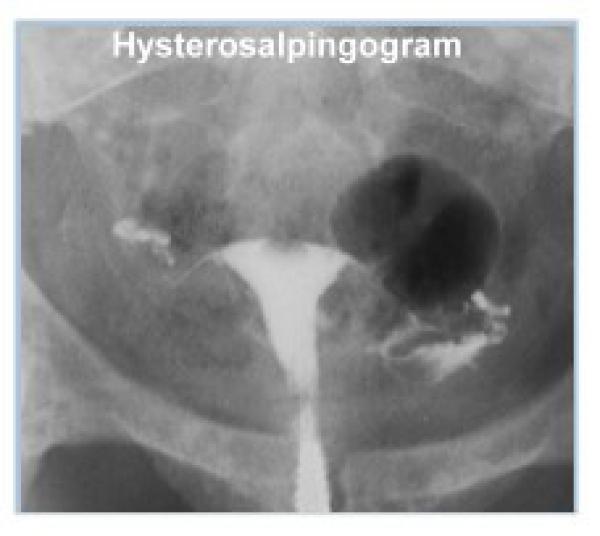

HSG nedir

Rahim Filmi (HSG) Nedir ? Histerosalpingografi (HSG) - rahim filmi jinekolojide rahim içinin ve kanalların yapısal ve işlevsel özelliklerini ince...